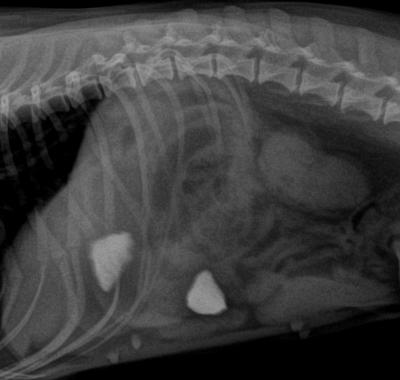

Tento kocourek zase asistoval při zabijačce. V jeho střevu můžete vidět kovovou svorku ve tvaru písmene "C".

Zde byla identifikace cizího tělesa snadná.

Nakonec byla ze střeva vyjmuta svorka i s kusem plastového obalu od salámu. Desetikoruna je přiložena jako měřítko.